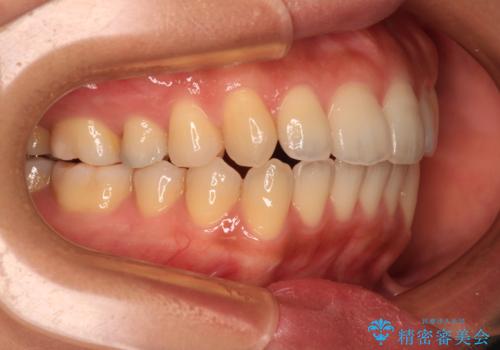

舌のトレーニングをしっかりと行ってくださり、前歯部のオープンバイトは大幅に改善されました。

もう少しでよりタイトに前歯が接触できそうでしたが、患者様がもう十分とのことで治療を終了しました。